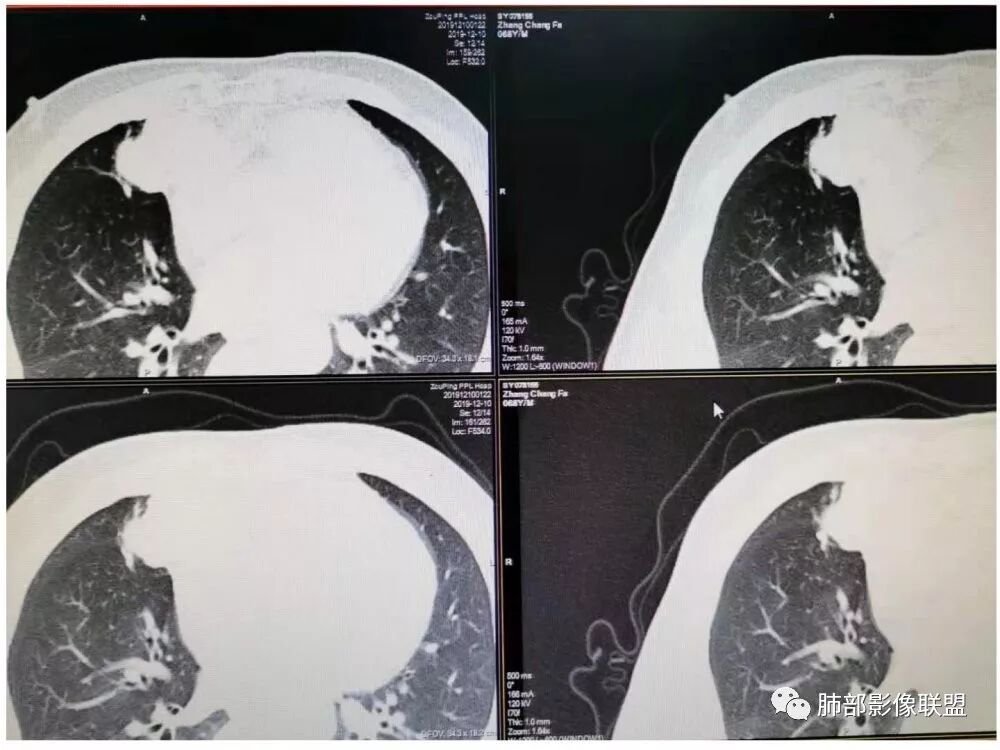

20例畸胎瘤钙化特点

有脂肪密度畸胎瘤

有脂肪,有钙化,钙化为条状,不是块状,偏心

多在前纵隔,可跨纵隔。就是从前跨到中的比较多

随机翻阅以上20个病例,都是畸胎瘤伴钙化的,发现只有2例钙化是团块状,且都是偏心的。其余18例钙化都是颗粒状、条状和包膜弧形钙化。有9例是多发钙化,且比较散,不聚集。总之,比较少会出现单发中心性的团块钙化。20例均没有,虽然样本少,但是均符合王兆宇老师说的规律。

第一种是弧形钙化,是囊性畸胎瘤的弧形钙化。

第二种条状钙化可能是血管钙化,脉管钙化。

第三种团块状或一颗颗的可能是牙齿,一般都不会太大,而且比较散在。

胸腺瘤钙化

大部分钙化还是包膜钙化和条状,结节状钙化,团块状钙化也比较少。位置中央,周围都可以。